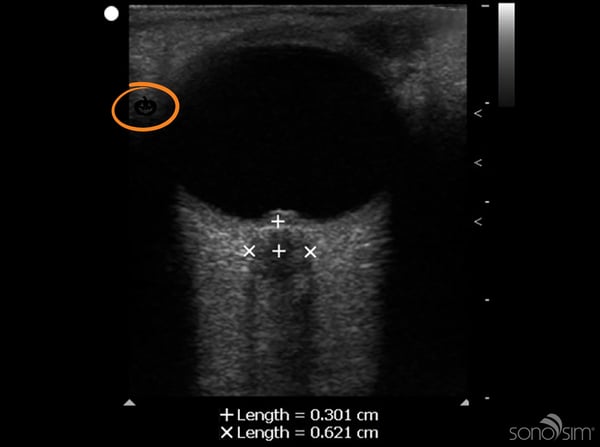

Look below to see the jack-o-lantern we hid in this ultrasound image.

Scan & Seek (2)-1